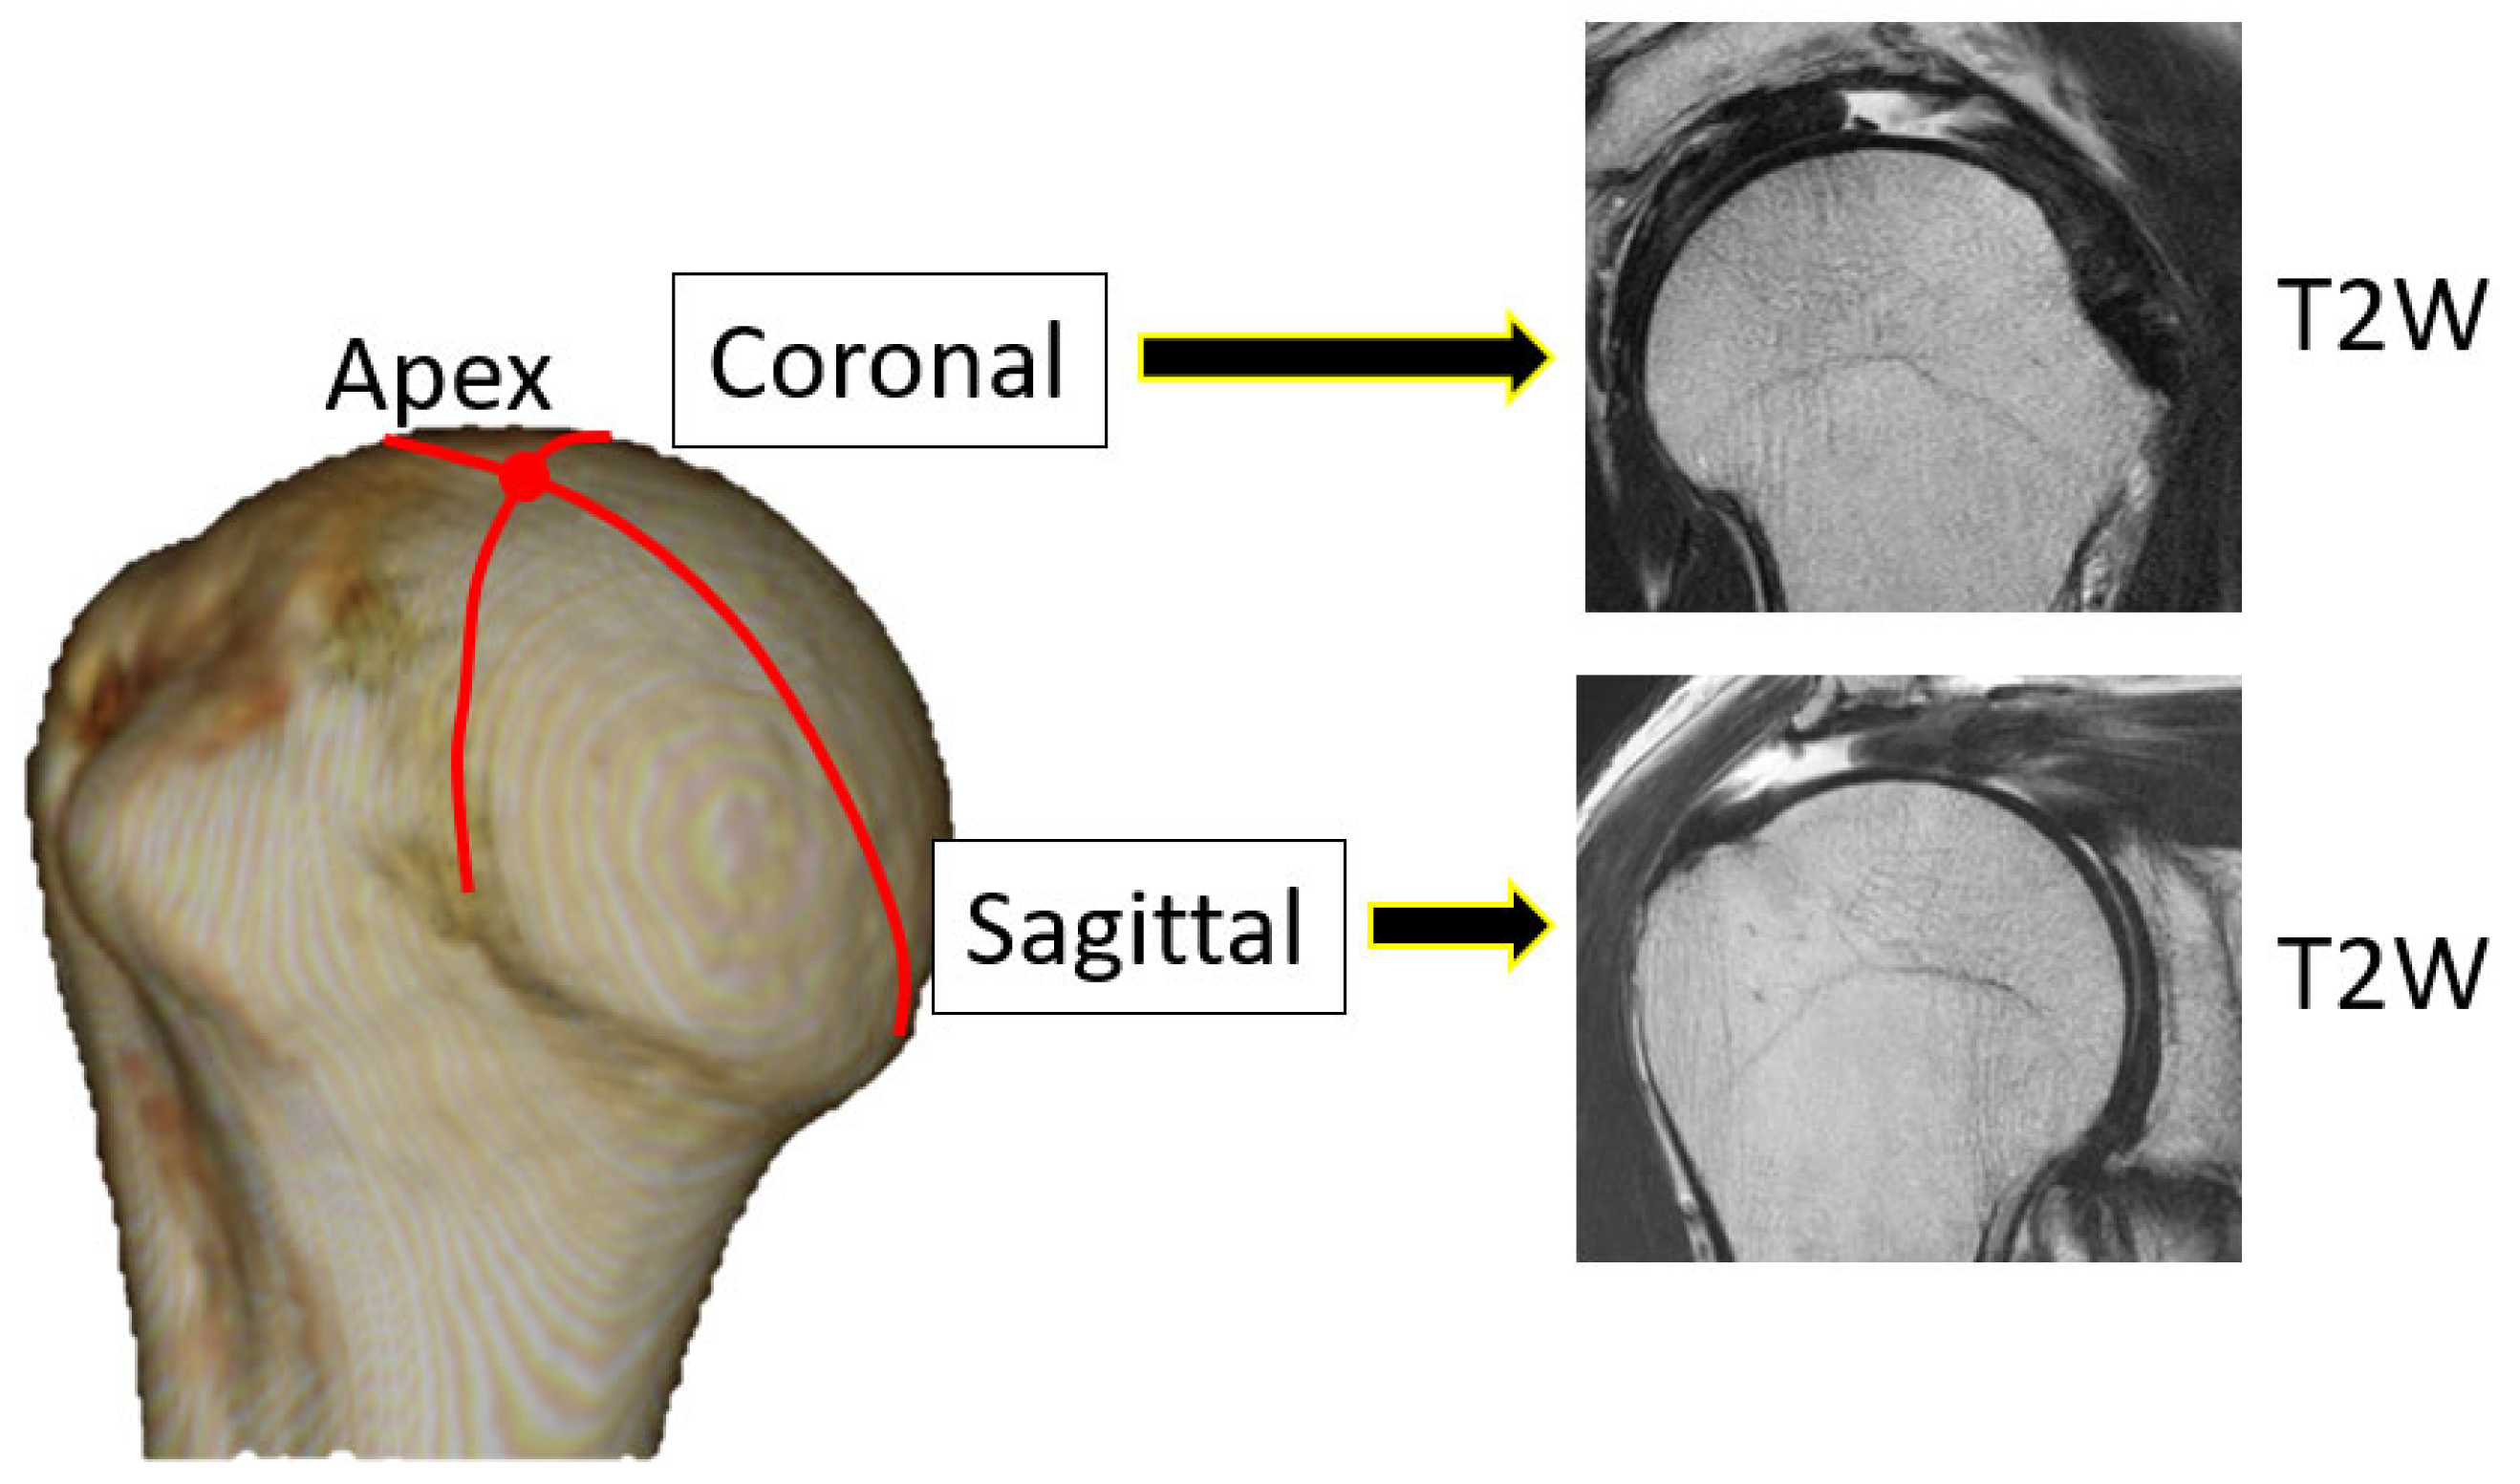

Tear length, cartilage thickness, and combined cartilage and subchondral bone thickness on the first and final MR images were measured using a RadiAnt DICOM-viewer (Medixant, Poznan, Poland). The rotator cuff tear length was defined from the lateral edge of the rotator cuff attachment to the lateral margin of the rotator cuff. Tear length was categorised based on the classification of DeOrio and Cofield [10]. The thickness of the glenoid cartilage was measured on the long and short axes (Figure 1). A T2-weighted image was used for the long axis, and a proton-weighted image was used for the short axis. The thickness of the humeral head cartilage was measured in the coronal and sagittal planes through the top of the humeral head using T2-weighted images (Figure 2). Since in the T2-weighted images, the cartilage and subchondral bone have a similar signal intensity, the combined thickness of the cartilage and subchondral bone was measured as the thickness. In the proton-weighted fat-suppressed image, the cartilage thickness, which is a high-signal region, was measured. For the humeral head cartilage measurement site, in the oblique coronal image, the humeral head was approximated to a circle, and the thickness was measured up to 150 degrees at every 30 degrees from the rotator cuff attachment (Figure 3). In the oblique sagittal image, the humeral head was approximated to a circle, and the thickness was measured at 30 degrees anterior, 30 degrees posterior, and 60 degrees posterior from the top of the head. The glenoid cartilage was measured from the anterior margin of the glenoid at 25%, 50%, and 75% of the anteroposterior glenoid length in axial view (Figure 4). In the oblique coronal image, measurements were taken from the superior margin of the glenoid at 25%, 50%, and 75% of the length from top to bottom. Since the maximum decrease in the cartilage thickness due to high-demand loaded exercise was 23%, a decrease of 30% or more in thickness was defined as cartilage thinning [11]. The primary outcome was the amount of change in cartilage thickness. The secondary outcome was the areas of cartilage thinning.

Figure 2. Measurement site and imaging condition of humeral head. T2WI: T2-weighted image.

Figure 3. The measurement points of the humeral head. (a) In the oblique coronal image, the humeral head was approximated to a circle, and the thickness was measured up to 150 degrees at every 30 degrees from the rotator cuff attachment. (b) In the oblique sagittal image, the humeral head was approximated to a circle, and the thickness was measured at 30 degrees anterior, 30 degrees posterior, and 60 degrees from the top of the head. Coronal: oblique coronal image, sagittal: oblique sagittal image.